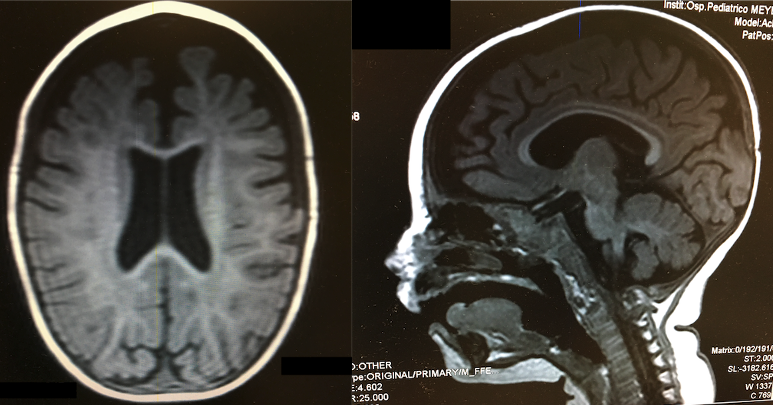

Alla valutazione clinica appariva in condizioni cliniche discrete, di colorito pallido. Presentava ipotono assiale e ritardo dell’acquisizione delle tappe evolutive, in particolare non manteneva la posizione seduta. Gli esami ematici mostravano un quadro di anemia macrocitica (Hb 6,5 g/d, MCV 101 fl, MCH 34,3 pg/ml), con neutropenia e piastrine ai limiti inferiori della norma. Allo striscio di sangue periferico si riscontravano neutrofili ipersegmentati. Visto il quadro neurologico, è stata eseguita una TC cranioencefalica, che ha mostrato atrofia del parenchima cerebrale con consensuale dilatazione degli spazi liquorali periencefalici.

La RM encefalica ha confermato l’atrofia della sostanza bianca biemisferica, con assottigliamento del corpo calloso (Figura 1). Estendendo l’anamnesi nutrizionale è emerso, inoltre, che la madre seguiva una dieta vegetariana fin dall’inizio della gravidanza. In considerazione dei dati anamnestici, del quadro di anemia macrocitica e del coinvolgimento della sostanza bianca encefalica, è stato quindi posto il sospetto di carenza di vitamina B12.